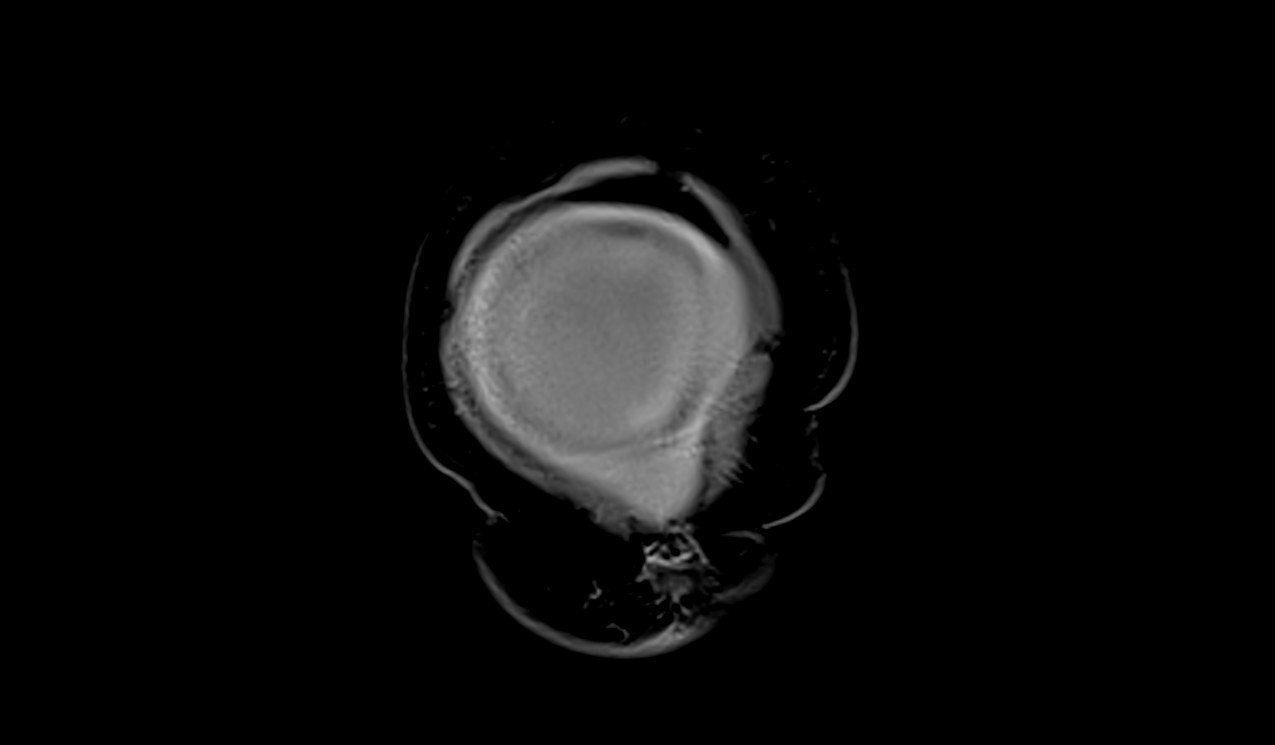

MRI Large abdomen and Pelvic Masses axial t1 dynaic image 2 - MRI